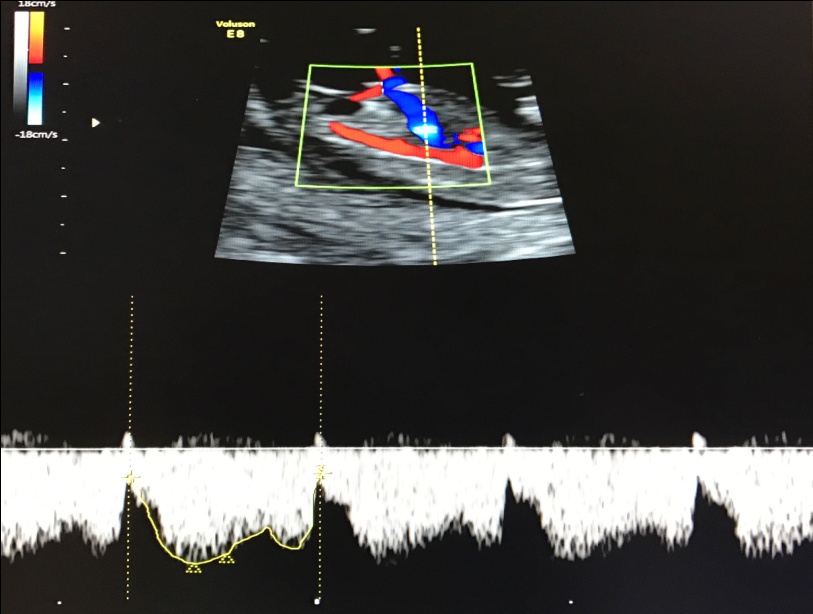

– кровоток в венозном протоке – это маленький сосуд в печени плода. При обратном (ретроградном) токе крови в данном сосуде можно предположить, что у плода хромосомный синдром, либо врожденный порок сердца.

Нормальный кровоток в венозном протоке

Но важно правильно получить этот кровоток и дать ему оценку. Для этого требуются определенные навыки и квалификация врача, которые подтверждаются ежегодной сертификацией FMF.. – кровоток через трикуспидальный клапан в сердце плода